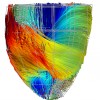

A Statistical Study of the Cardiac Diffusion Tensor Images

While the main geometrical arrangement of myofibers has been known for decades, its variability between subjects and species still remains largely unknown. Understanding this variability is not only important for a better description of physiological principles but also for the planning of patient-specific cardiac therapies. Furthermore, the knowledge of the relation between the myocardium shape and its myofiber structure is an important and required stage towards the construction of computational models of the heart since the fiber orientation plays a key role when simulating the electrical and mechanical function of the heart. The knowledge about fibre orientation has been recently eased with the use of Diffusion Tensor Imaging (DTI) since there is a correlation between the myocardium fibre structure and diffusion tensors. DTI also has the advantage to provide directly this information in 3D with a high resolution, unfortunately it is not available in vivo due to the cardiac motion. A statistical study of ex vivo cardiac DTI will help in understanding the cardiac fibre structure and in modeling the electromechanical behavior of the heart.

While the main geometrical arrangement of myofibers has been known for decades, its variability between subjects and species still remains largely unknown. Understanding this variability is not only important for a better description of physiological principles but also for the planning of patient-specific cardiac therapies. Furthermore, the knowledge of the relation between the myocardium shape and its myofiber structure is an important and required stage towards the construction of computational models of the heart since the fiber orientation plays a key role when simulating the electrical and mechanical function of the heart. The knowledge about fibre orientation has been recently eased with the use of Diffusion Tensor Imaging (DTI) since there is a correlation between the myocardium fibre structure and diffusion tensors. DTI also has the advantage to provide directly this information in 3D with a high resolution, unfortunately it is not available in vivo due to the cardiac motion. A statistical study of ex vivo cardiac DTI will help in understanding the cardiac fibre structure and in modeling the electromechanical behavior of the heart.